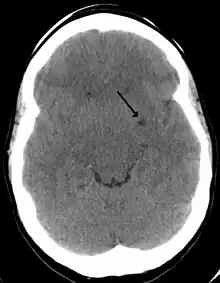

Les espaces de Virchow-Robin, encore appelés espaces périvasculaires, doivent leur nom à Rudolf Virchow et Charles Philippe Robin. Ce sont des espaces, souvent uniquement virtuels, qui entourent les vaisseaux sanguins pendant une courte distance alors qu'ils entrent dans le cerveau. Ces espaces se trouvent donc entre d'une part la paroi des vaisseaux et d'autre part l'intima pia qui est la couche avasculaire de la pie-mère. Ils forment des sortes de gaines, sous arachnoïdienne et sous piale, entourant les artérioles pénétrant dans le cortex, et remplies de LCR.

Espace LCR de Virchow-Robin en 2010.